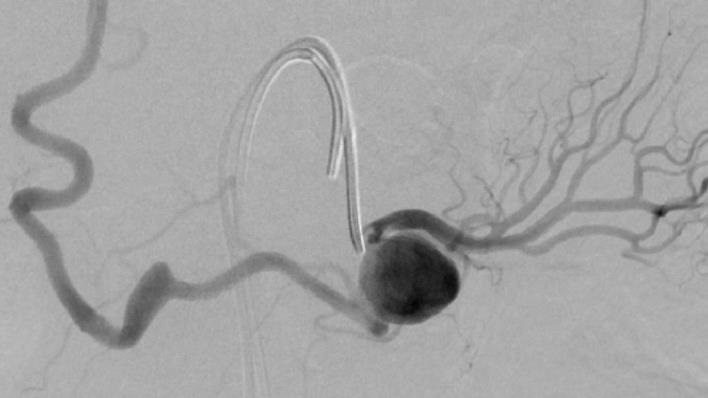

肾动脉瘤重塑技术

|

肾动脉瘤 |

微导管头进入动脉瘤腔后用球囊(4mm x 20mm)充盈后封住瘤颈的口;释放微弹簧圈到动脉瘤囊内 |

微弹簧圈对瘤囊致密填塞

coil N=41 |

栓塞后造影显示瘤腔消失 |